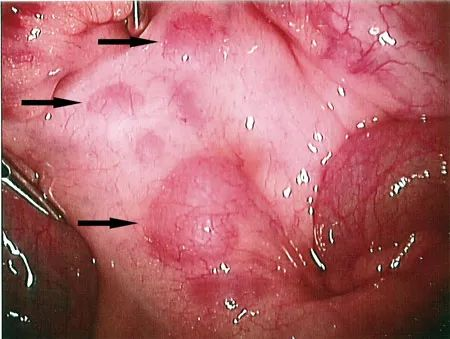

孩子发生腹痛,按压孩子腹部时会发现,孩子不能准确描述腹痛位置,时而右下腹,时而腹部其他部位,尤其脐周。有时右下腹压痛伴有反跳痛及肌紧张者,可能需要给予B超等特殊检查,以便与急性阑尾炎相鉴别。部分患儿还常伴有咽部充血、扁桃体肿大、颈部淋巴结增大等炎性体征。

当孩子发生腹痛时,家长就要警惕是不是肠系膜淋巴结炎的发生。我们可以带孩子来医院找专业儿科医生为孩子进行详细问诊和查体,必要时做专项检查,腹部超声能够清晰显示淋巴结,可为临床诊断及随访观察提供安全可靠的依据,因此临床上公认可作为肠系膜淋巴结炎检查的首选方法。